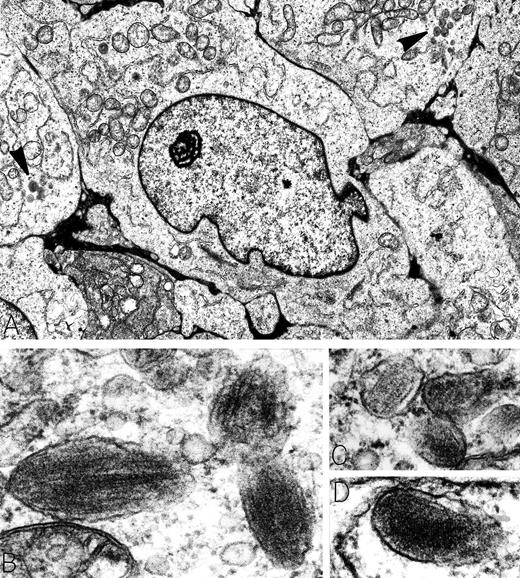

A 29-year-old man presented with a 20-pound weight loss and was found to have a large retroperitoneal mass. Electron microscopy was diagnostic for metastatic amelanotic melanoma, characterized by large tumor cells with prominent nucleoli and focal clusters of membrane-bound, ellipsoid granules (arrowheads in A). Higher magnification of these organelles showed that they were premelanosomes containing perpendicular striated filaments (B and C) or parallel lamellar arrays (D). Extremely electron-dense melanin was absent from the premelanosomes. Immunoperoxidase stains of tumor cells were positive for the melanoma-associated antigen HMB-45 and negative for leukocyte common antigen, B-cell antigen (CD20 and CD19), T-cell antigens (CD2, CD3, CD4, CD5, and CD8), and lymphoid activation antigens (CD30 and CD15). Retrospectively, the patient was stated to have fair skin, numerous freckles, and red hair; no history of excesssive sunburns or skin lesions was elicited. Original magnifications: (A) ×8,000; (B) ×90,000; (C) ×71,500; and (D) ×91,000. (Courtesy of Ann M. Dvorak, MD, Department of Pathology, Beth Israel Deaconess Medical Center, 330 Brookline Ave, Boston, MA 02215.)